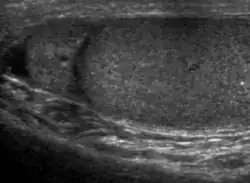

![]() Sonography of a normal testis. The normal testis presents as a structure having homogeneous, medium level, granular echotexture. The mediastinum testis appears as the

hyperechoic region located at the periphery of the testis as seen in this figure. | |

The normal adult testis is an ovoid structure measuring 3 cm in anterior-posterior dimension, 2–4 cm in width, and 3–5 cm in length. The weight of each testis normally ranges from 12.5 to 19 g. Both the sizes and weights of the testes normally decrease with age. At ultrasound, the normal testis has a homogeneous, medium-level, granular echotexture. The testicle is surrounded by a dense white fibrous capsule, the tunica albuginea, which is often not visualized in the absence of intrascrotal fluid. However, the tunica is often seen as an echogenic structure where it invaginates into the testis to form the mediastinum testis. In the testis, the seminiferous tubules converge to form the rete testes, which is located in the mediastinum testis. The rete testis connects to the epididymal head via the efferent ductules. The epididymis is located posterolateral to the testis and measures 6–7 cm in length. At sonography, the epididymis is normally iso- or slightly hyperechoic to the normal testis and its echo texture may be coarser. The head is the largest and most easily identified portion of the epididymis. It is located superolateral to the upper pole of the testicle and is often seen on paramedian views of the testis. The normal epididymal body and tail are smaller and more variable in position.